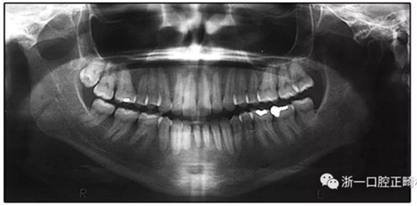

患者是一名39歲的白人婦女,病史不明。她主訴是她的右側(cè)顳下關(guān)節(jié)有不適癥狀,并希望改善她的笑容。她有一個對稱的臉型和一個II類2分類的微笑。她的側(cè)貌是凸的,90°的鼻唇角和骨性下頜骨發(fā)育不足??趦?nèi),上頜中線與面部重合,但下頜中線向右側(cè)偏移5mm;存在6mm的深覆蓋。她的兩側(cè)都是I類磨牙關(guān)系,左側(cè)是I類尖牙關(guān)系,右側(cè)是完全的II類尖牙關(guān)系。下頜右側(cè)第二前磨牙先天性缺失(圖1和圖2)。最初的全景片顯示了足夠的骨質(zhì)水平和全部的第三磨牙(圖3)。治療前的頭影測量片片和相應(yīng)的頭影測量圖(圖3)證實ANB為7°,Wits評估為6 mm的骨性II類錯合(表)。上頜切牙相對與面部和顱底的位置很好。下頜切牙前傾。診斷為II類2分類錯合畸形,伴有骨性下頜發(fā)育不足,右側(cè)顳下頜關(guān)節(jié)癥狀,下頜中線向右側(cè)偏移5mm,先天性右下第二前磨牙缺失。

圖3. 治療前頭影側(cè)位片,頭影測量描跡圖和全口X光片